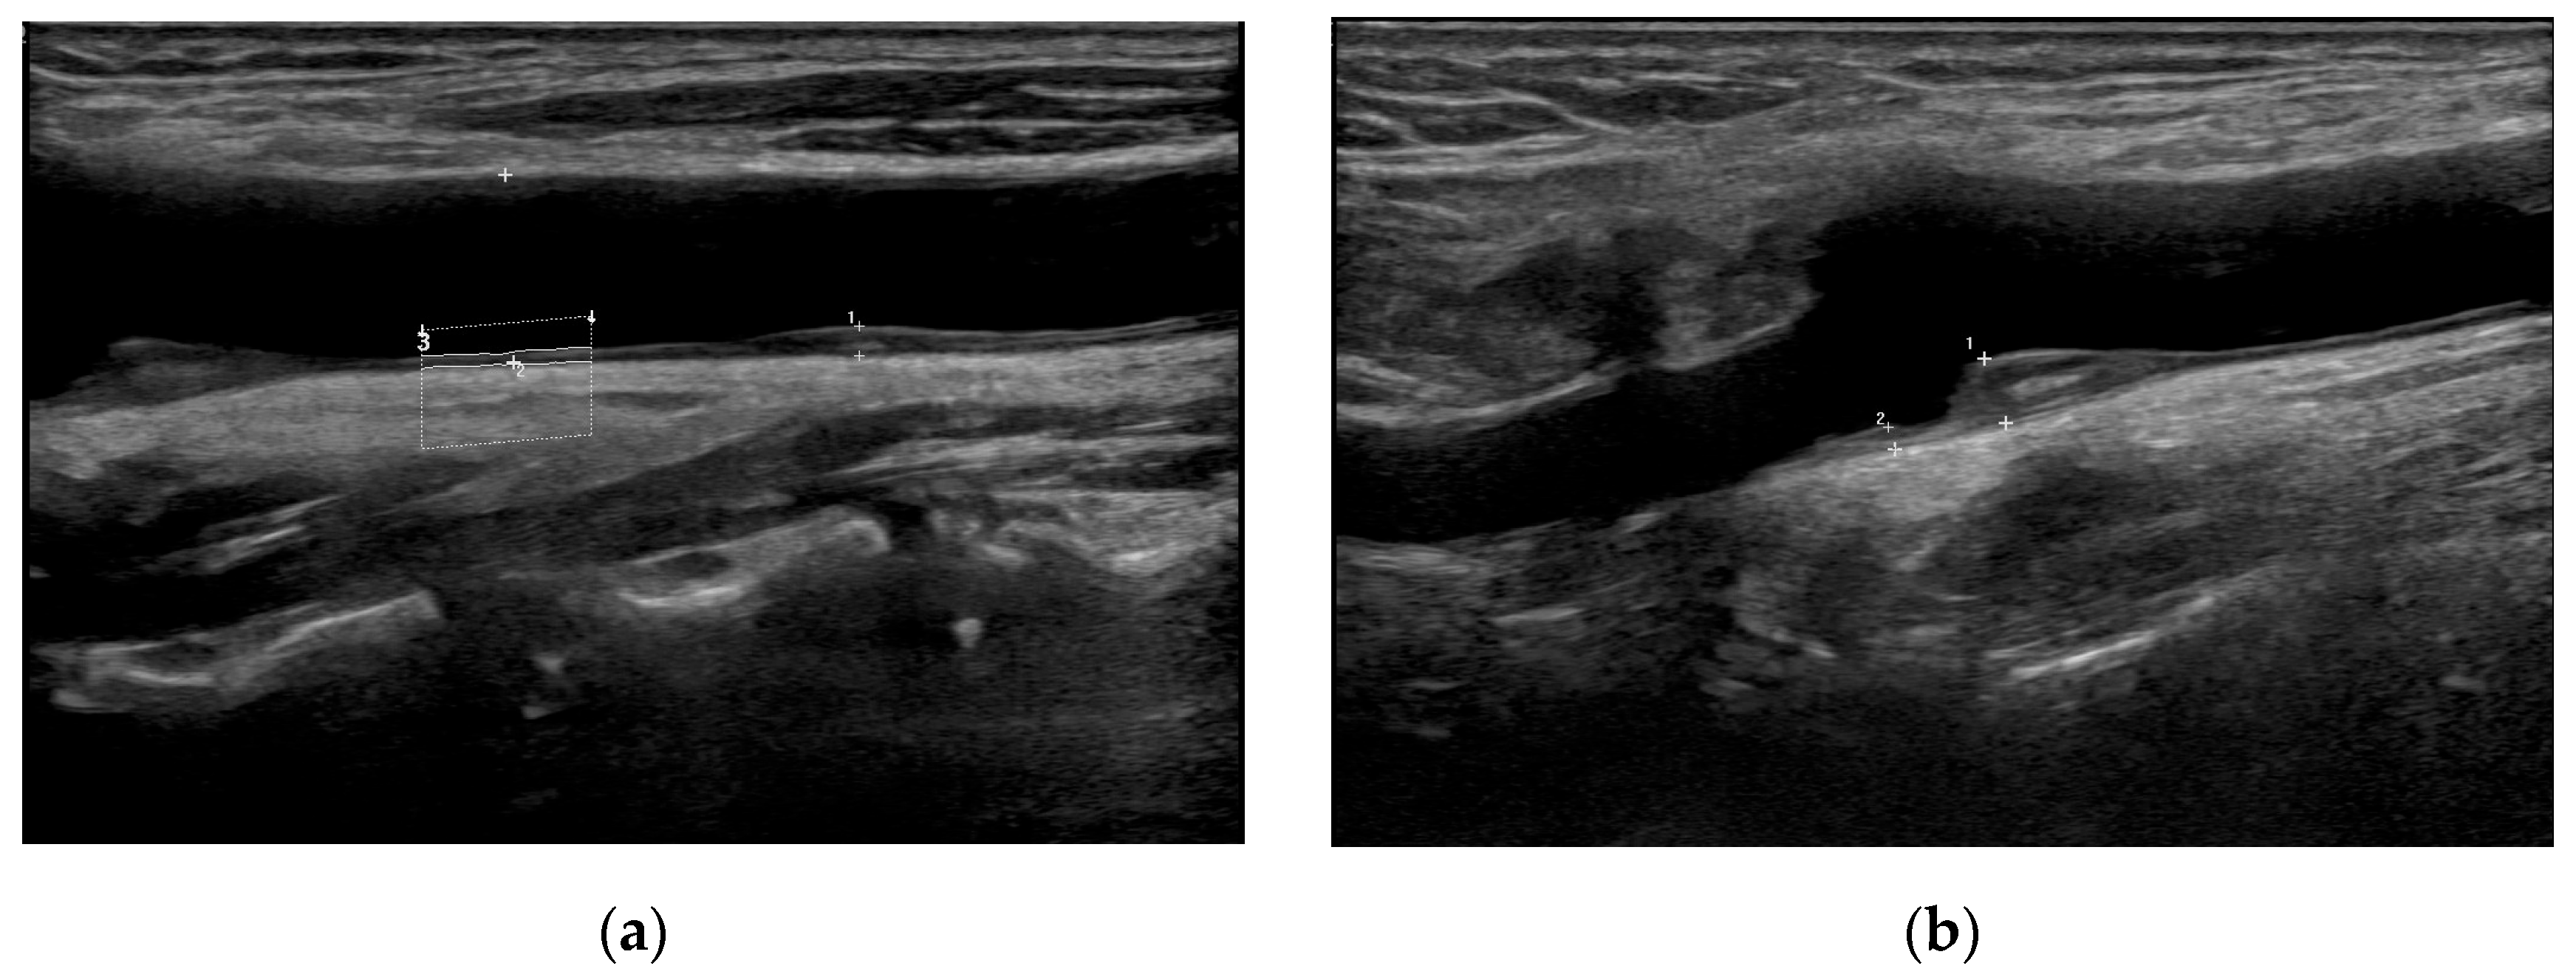

2.2. Carotid Assessments

- Fernandez-Alvarez, V.; Linares Sanchez, M.; Lopez Alvarez, F.; Suarez Nieto, C.; Makitie, A.A.; Olsen, K.D.; Ferlito, A. Evaluation of intima-media thickness and arterial stiffness as early ultrasound biomarkers of carotid artery atherosclerosis. Cardiol. Ther. 2022, 11, 231–247. [Google Scholar] [CrossRef] [PubMed]

- Johri, A.M.; Nambi, V.; Naqvi, T.Z.; Feinstein, S.B.; Kim, E.S.H.; Park, M.M.; Becher, H.; Sillesen, H. Recommendations for the assessment of carotid arterial plaque by ultrasound for the characterization of atherosclerosis and evaluation of cardiovascular risk: From the American Society of Echocardiography. J. Am. Soc. Echocardiogr. 2020, 33, 917–933. [Google Scholar] [CrossRef] [PubMed]